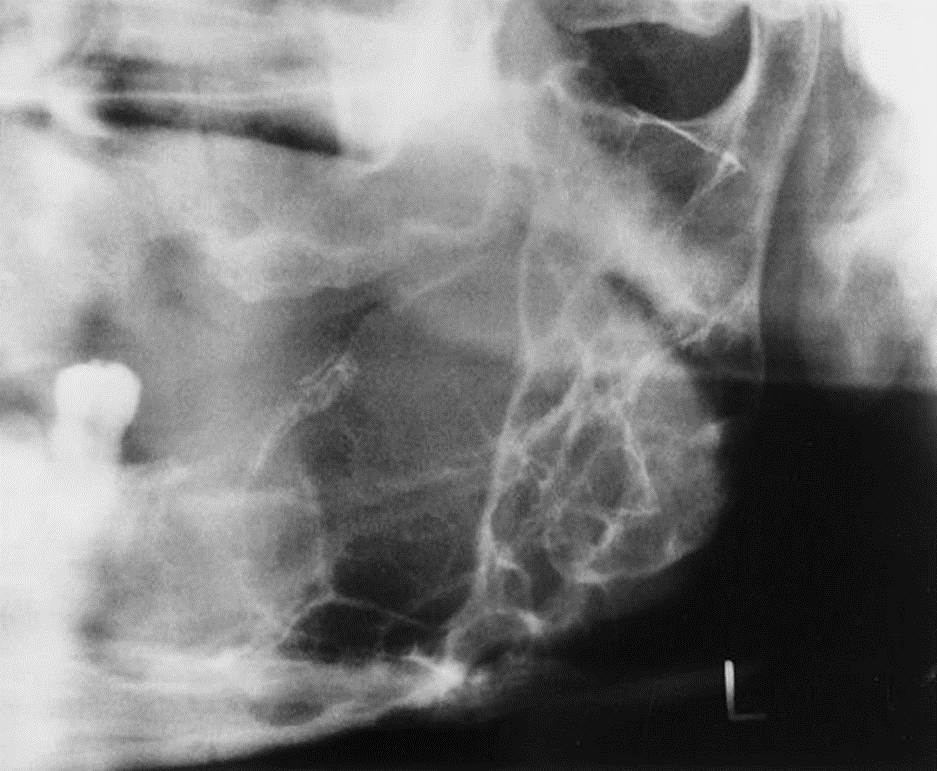

3. This is a 35-year-old asymptomatic woman who has slight buccal and palatal enlargement of the alveolar bone in this area. Other studies indicated portions of the zygoma were involved. This condition was first detected at age 19 years and is slowly progressive. Her alkaline phosphatase was normal to high-normal, and her serum calcium was normal.

What is your diagnostic impression?